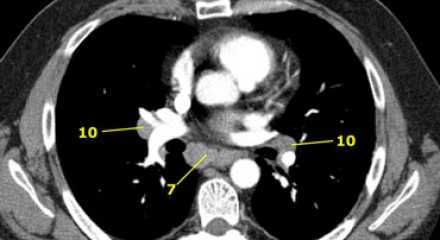

7. Подкаринальные лимфатические узлы

Эти лимфатические узлы расположены ниже уровня бифуркации трахеи (карины), но не относятся к нижнедолевым бронху и артерии. Справа они располагаются каудальнее нижней стенки промежуточного бронха. Слева они располагаются каудальнее верхней стенки нижнедолевого бронха. Слева лимфатический узел 7 группы справа от пищевода.